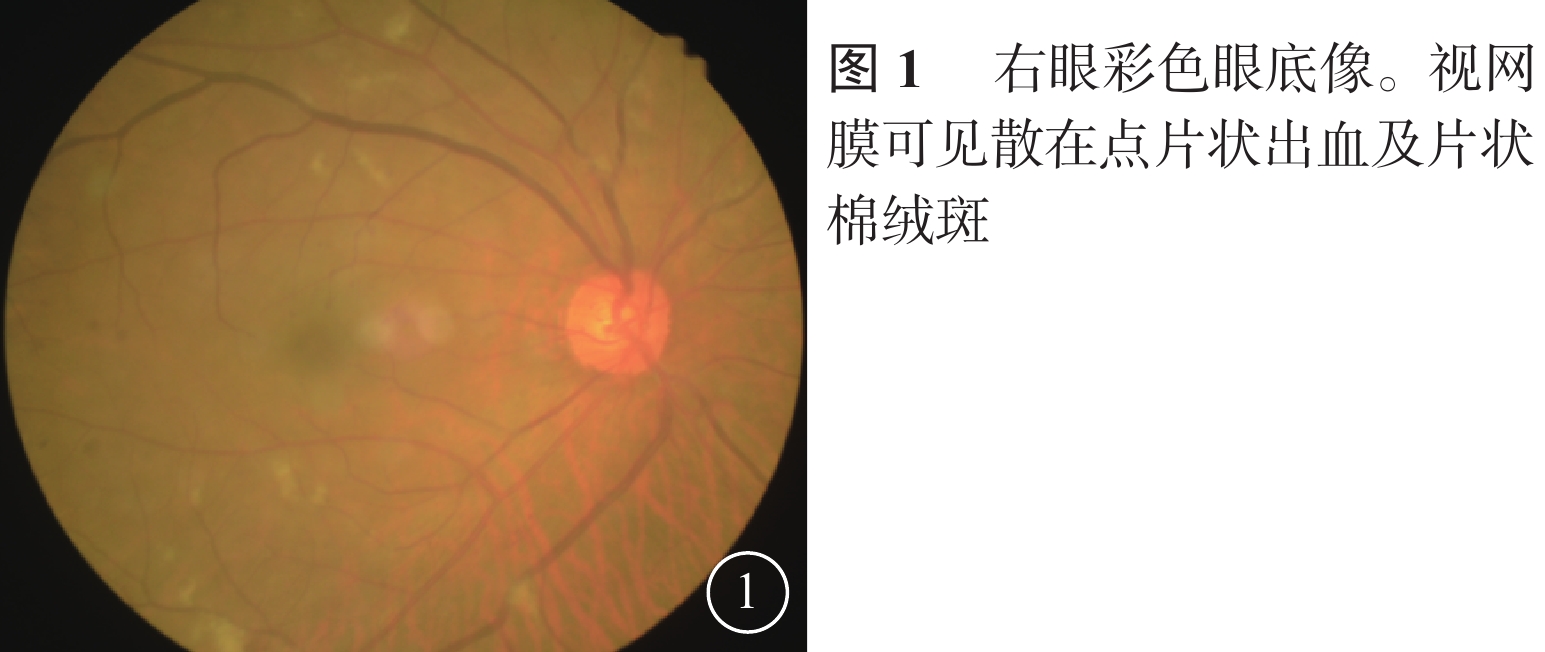

患者男,65歲。因右眼視物不見1周于2016年10月20日來我院就診。1周前無意中發現右眼視物不見,無眼紅、痛、畏光、流淚;自行使用芐達賴氨酸(商品名:莎普愛思)滴眼液滴眼無效而就診于外院。診斷為右眼新生血管性青光眼(NVG)?右眼視網膜病變(性質?);雙眼老年性白內障。既往高血壓病史8年,口服藥物治療。否認糖尿病、冠心病等其他全身病史。眼科檢查:右眼視力光感/眼前;左眼視力0.6,不能矯正。右眼眼壓17.3 mmHg(1 mmHg= 0.133 kPa),左眼眼壓12.7 mmHg。右眼前房深淺正常,周邊前房1 角膜厚度;瞳孔藥物性散大,邊緣全周可見虹膜新生血管(NVI),無后粘連;晶狀體混濁;玻璃體輕度混濁。眼底視盤邊界清楚,顏色橘紅,血管走形及比例基本正常;視網膜可見散在點片狀出血及片狀棉絨斑,黃斑中心凹反光不清(圖1)。左眼除晶狀體混濁、玻璃體輕度混濁,黃斑中心凹反光不清外,其余眼前節及眼底檢查未見明顯異常。熒光素眼底血管造影(FFA)檢查,右眼脈絡膜背景熒光充盈遲緩,視網膜動靜脈循環時間明顯延長(圖2)。光相干斷層掃描檢查,右眼后極部視網膜增厚,視網膜內層間反射信號大部分增強;左眼黃斑中心凹形態不規則。彩色超聲多普勒血流成像(CDFI)檢查,雙側頸總動脈、頸內動脈多發斑塊;右側頸內動脈管腔狹窄,約70%~99%(圖3)。頸動脈CT血管造影(CTA)檢查,顱內動脈硬化,可疑右側頸內動脈C1段重度狹窄;可疑兩側基底節區、右側丘腦腔隙性缺血灶。診斷:右眼眼缺血綜合征(OIS);雙眼老年性白內障;高血壓病。給予右眼玻璃體腔注射雷珠單抗0.05 ml治療。治療后3 d,視力數指/66 cm,眼壓15.0 mmHg;NVI完全消退。行右眼全視網膜激光光凝(PRP)治療。PRP治療后14 d檢查,右眼視力0.1;眼壓13.0 mmHg。轉血管外科行右側頸動脈內膜剝脫手術。手術后1個月復查,右眼視力0.4。FFA檢查,視網膜循環時間明顯改善(圖4)。

患者男,65歲。因右眼視物不見1周于2016年10月20日來我院就診。1周前無意中發現右眼視物不見,無眼紅、痛、畏光、流淚;自行使用芐達賴氨酸(商品名:莎普愛思)滴眼液滴眼無效而就診于外院。診斷為右眼新生血管性青光眼(NVG)?右眼視網膜病變(性質?);雙眼老年性白內障。既往高血壓病史8年,口服藥物治療。否認糖尿病、冠心病等其他全身病史。眼科檢查:右眼視力光感/眼前;左眼視力0.6,不能矯正。右眼眼壓17.3 mmHg(1 mmHg= 0.133 kPa),左眼眼壓12.7 mmHg。右眼前房深淺正常,周邊前房1 角膜厚度;瞳孔藥物性散大,邊緣全周可見虹膜新生血管(NVI),無后粘連;晶狀體混濁;玻璃體輕度混濁。眼底視盤邊界清楚,顏色橘紅,血管走形及比例基本正常;視網膜可見散在點片狀出血及片狀棉絨斑,黃斑中心凹反光不清(圖1)。左眼除晶狀體混濁、玻璃體輕度混濁,黃斑中心凹反光不清外,其余眼前節及眼底檢查未見明顯異常。熒光素眼底血管造影(FFA)檢查,右眼脈絡膜背景熒光充盈遲緩,視網膜動靜脈循環時間明顯延長(圖2)。光相干斷層掃描檢查,右眼后極部視網膜增厚,視網膜內層間反射信號大部分增強;左眼黃斑中心凹形態不規則。彩色超聲多普勒血流成像(CDFI)檢查,雙側頸總動脈、頸內動脈多發斑塊;右側頸內動脈管腔狹窄,約70%~99%(圖3)。頸動脈CT血管造影(CTA)檢查,顱內動脈硬化,可疑右側頸內動脈C1段重度狹窄;可疑兩側基底節區、右側丘腦腔隙性缺血灶。診斷:右眼眼缺血綜合征(OIS);雙眼老年性白內障;高血壓病。給予右眼玻璃體腔注射雷珠單抗0.05 ml治療。治療后3 d,視力數指/66 cm,眼壓15.0 mmHg;NVI完全消退。行右眼全視網膜激光光凝(PRP)治療。PRP治療后14 d檢查,右眼視力0.1;眼壓13.0 mmHg。轉血管外科行右側頸動脈內膜剝脫手術。手術后1個月復查,右眼視力0.4。FFA檢查,視網膜循環時間明顯改善(圖4)。